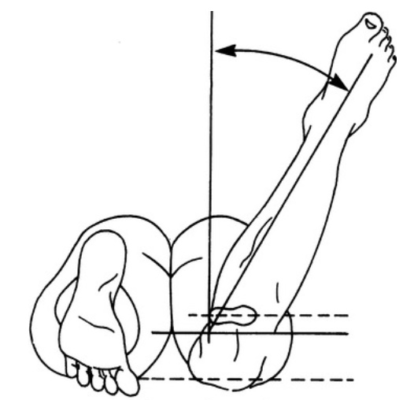

Xoay của xương chày thể hiện qua mối tương quan giữa đường liên hai mắt cá (transmalleolar axis) với với trục dọc của đùi. Có thể đánh giá điều này thông qua đo trục đùi -bàn chân (trục đùi- bàn chân cũng thay đổi khi có sự xoay của phần bàn chân sau, hind foot). Trẻ nhũ nhi thường có góc đùi- bàn chân xoay trong 5° và chuyển sang xoay ngoài khoảng 10° lúc trẻ 8 tuổi. Cũng có thể đo góc đường giữa trục xương đùi với đường liên mắt cá.

Đánh giá biến dạng xoay ở đoạn bàn chân sử dụng đường chia đôi (lòng) bàn chân (bisector line) sau từ gót chân. Đường này thường đi qua khoảng kẽ ngón II-III, và lệch vào trong hoặc ra ngoài chứng tỏ bàn chân trước bị khép hoặc dạng.